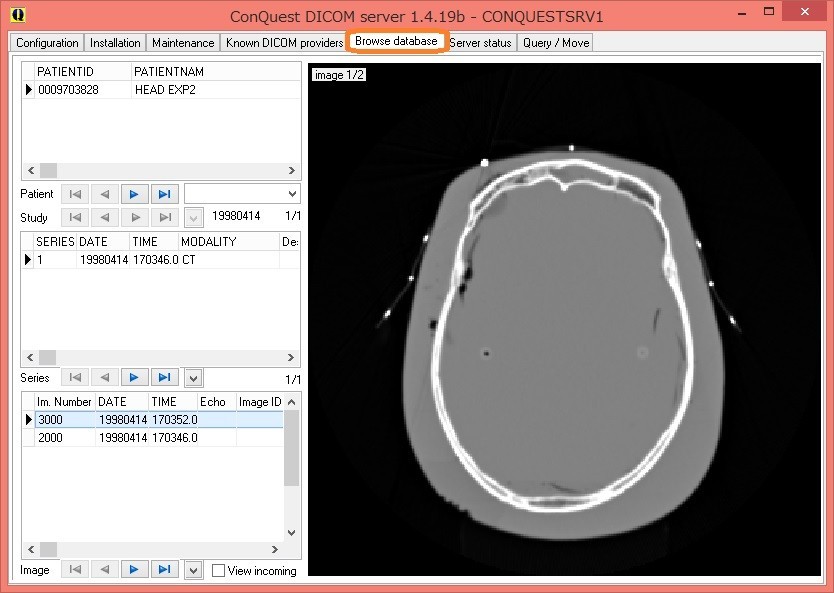

「Brows Database」のタブを選択して、サンプル画像を見てみましょう。